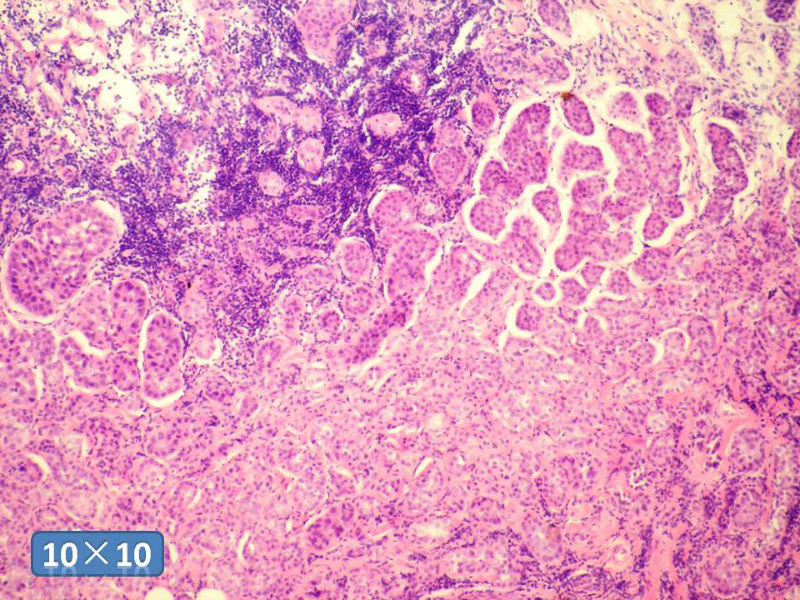

女性,50岁,乳腺肿物,冰冻切片(图1-25)

HE